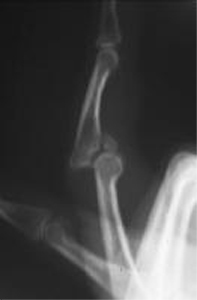

Boutonniere Deformity

Zone III extensor tendon injury

rupture of central slip

open or avusion treat open (

closed treat closed ext PIP splint

reconstruction vs terminal tendon tenotomy (Fowler) if fails